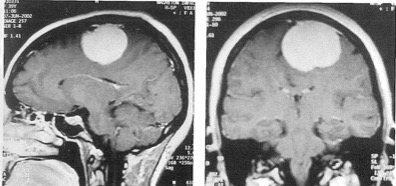

Εικόνες 1α,1β. Παροβελιαίο μηνιγγίωμα της κυρτότητας, δηλ. κοντά στη μεσότητα και κοντά στην επιφάνεια του εγκεφάλου και του κρανίου.